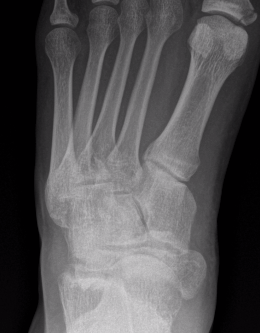

Imaging

Acute, minimally displaced navicular fracture

Acute displaced navicular fracture